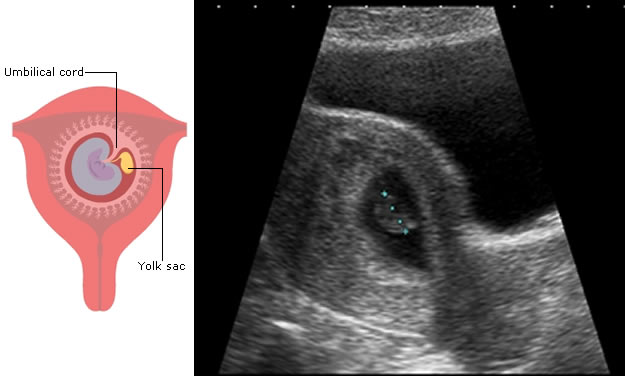

The first feature to be seen on ultrasound is the gestation sac, which will become the amniotic and chorionic sacs. These contain fluid and are seen as black on ultrasound.

The trophoblast is specially modified embryonic tissue which allows the pregnancy to implant into the uterine wall. It is almost white on ultrasound and part of it will form the placenta.

The embryo itself is usually only seen after 6 weeks following the last period.

Note: in this ultrasound image of an early pregnancy, the sonographer has made a measurement of the length of the developing baby (dotted blue line). You will learn about this measurement later in this session.